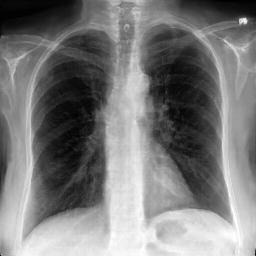

Image Reconstruction. Table 1 shows that the co-training scheme outperforms the \mathcal{E}-training approach in reconstruction accuracy, as indicated by higher PSNR and IW_SSIM scores, highlighting the benefits of joint optimization for enhancing reconstruction quality. The results are further validated by the visual comparison in Fig. 2, where the co-training scheme recovers input images with finer details and higher fidelity. In contrast, the \mathcal{E}-training scheme exhibits noticeable discrepancies when compared to the original images.

Refer to caption

XRX_{R}

Co-training

\mathcal{E}-training

Fig. 2: Reconstruction results. The first row displays the real images XRX_{R}. The last two rows show the reconstructed images X^R\hat{X}_{R} produced by the proposed co-training scheme and the \mathcal{E}-training scheme, respectively.